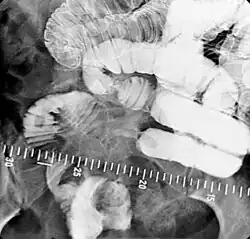

Enteroclysis

Enteroclysis is also known as small bowel enema.[21] It has been largely replaced by magnetic resonance enterography/enteroclysis[13] and computed tomography enterography/enteroclysis.[22]

In addition to fasting for 8 hours prior to examination, a laxative may also be necessary for bowel preparation and cleansing.[12] The main aim of this study is to distend the proximal bowel through infusion of large amount of barium suspension. Otherwise, the distension of distal small bowel is generally similar with small bowel follow-through. Therefore, there is a need to pass a tube through the nose into the jejunum (nasojejunal tube) to administer large amount of contrast. This can be unpleasant to the subject, requires more staff, longer procedural time, and higher radiation dose when compared to small bowel follow-through. The indications for enteroclysis are generally similar to small bowel follow-through. Barium suspensions such as diluted E-Z Paque 70% and Baritop 100% can be used. After that, 600 ml of 0.5% methylcellulose is administered after 500 ml of 70% barium suspension is given. Bilbao-Dotter tube and Silk tube can be used to administer barium suspension. The subject should be fasted overnight, any antispasmodic drugs should be stopped one day before the examination, and Tetracaine lozenges can be used 30 minutes before the procedure to numb the throat for nasojejunal tube insertion.[13]

The filling of the small intestines can be viewed continuously using fluoroscopy, or viewed as standard radiographs taken at frequent intervals. The technique is a double-contrast procedure that allows detailed imaging of the entire small intestine. However, the procedure may take 6 hours or longer to complete and is quite uncomfortable to undergo.[23]

- Enteroclysis has shown to be very accurate in diagnosing small bowel diseases, with a sensitivity of 93.1% and specificity of 96.9%. It permits detection of lesion which may not be seen with other imaging techniques.[7] There is no significant difference in terms of detection of clinically significant findings, sensitivity or specificity between enteroclysis and CT enterography.[1] Enteroclysis compares favorably with wireless capsule endoscopy and double-balloon endoscopy in the diagnosis of mucosal abnormalities of the small bowel.[24]